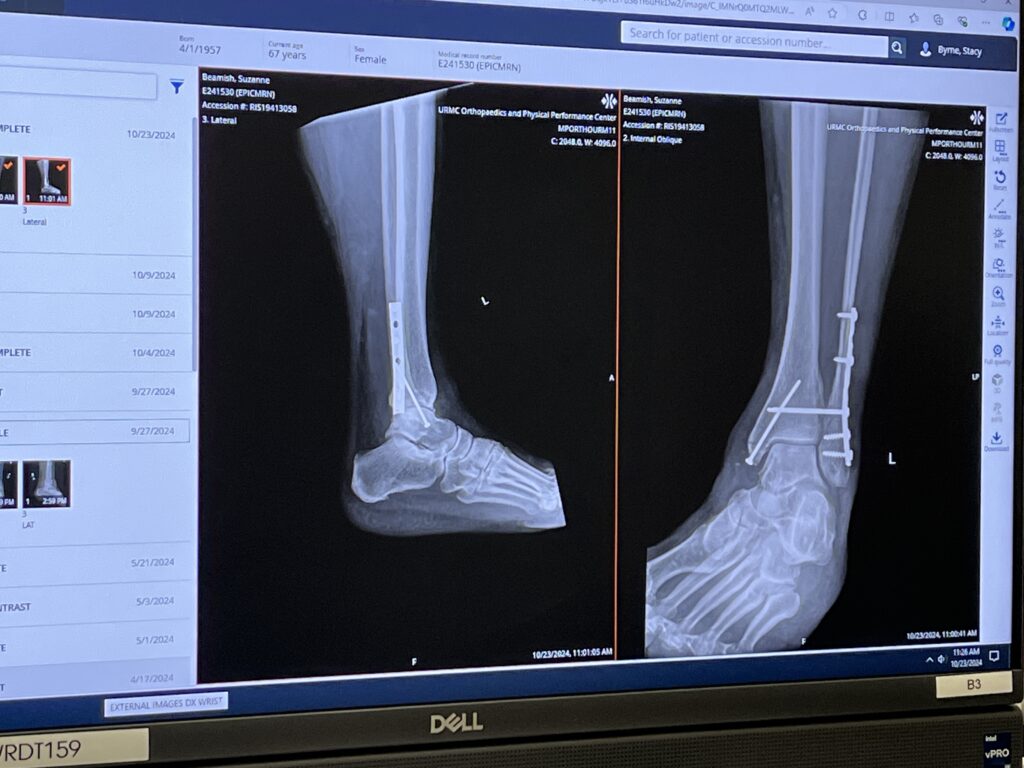

The finished product